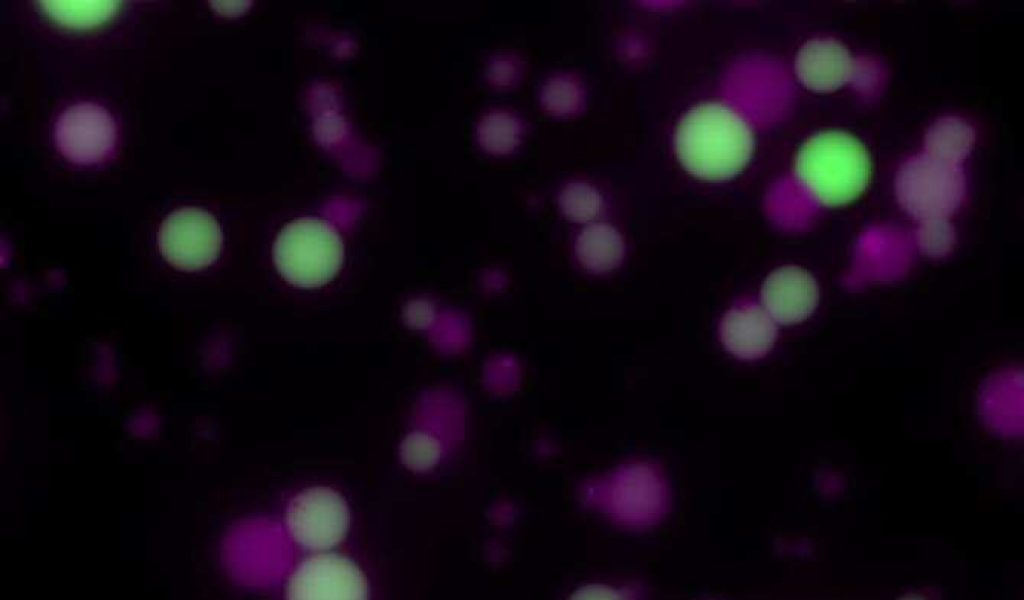

Imagen: Las células sintéticas vistas mediante un microscopio de fluorescencia. Las células en verde son las que han expresado una proteína. (Foto: Ellen Parkes et al. CC BY-SA)

Las células sintéticas empleadas son como las células naturales en algunos aspectos, pero no están vivas realmente. A grandes rasgos, poseen una membrana grasa que contiene componentes químicos o biológicos como el ADN. Dependiendo del ADN en su interior, las células pueden producir cualquier proteína necesaria.

El equipo aplicó un campo magnético alterno, lo que provocó que las nanopartículas magnéticas calentaran únicamente su entorno inmediato, lo que resultó en la activación del ADN dentro de la célula sintética para producir una proteína.